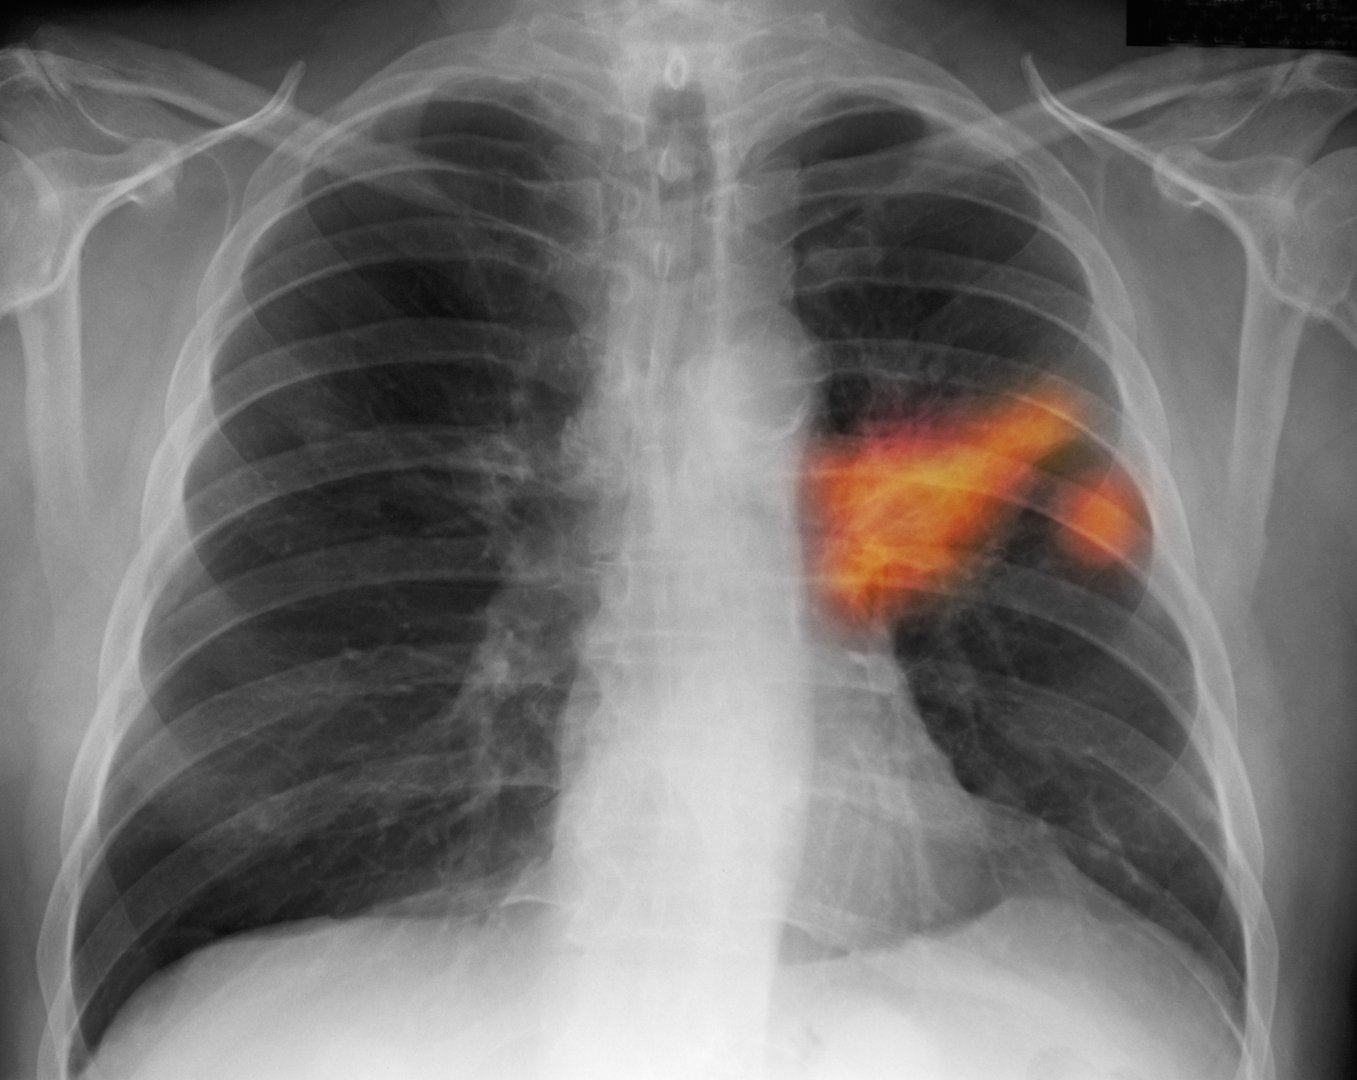

وتبين أن الفيروس قد يزيد قليلا من خطر الإصابة بسرطان الرئة، خاصة لدى المدخنين، وذلك من خلال سلسلة من التفاعلات البيولوجية التي يقودها بروتين “سبايك” الشهير.

ووجد الباحثون أن الناجين من “كوفيد-19” أظهروا زيادة طفيفة لكنها ملحوظة إحصائيا في خطر الإصابة بسرطان الرئة، حيث ارتفع الخطر النسبي بنسبة 22%. وكان هذا الخطر مرتفعا بشكل خاص بين المدخنين الحاليين.

ومن المثير للاهتمام أن الدراسة لم تجد زيادة مماثلة في خطر الإصابة بسرطان الفم أو المثانة، ما يشير إلى أن الفيروس لديه تفضيل خاص للتأثير على أنسجة الرئة دون غيرها.